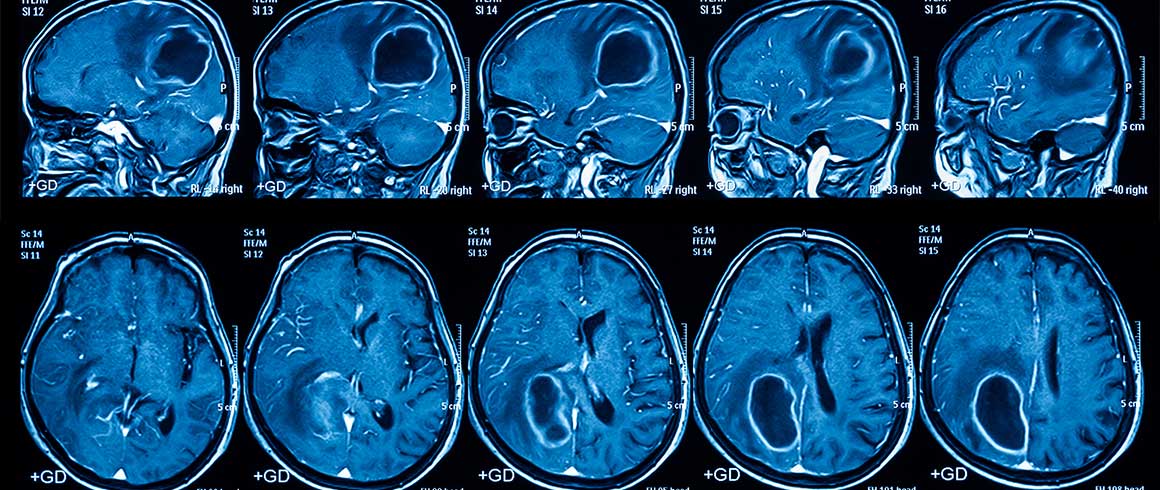

Il glioblastoma è il tumore cerebrale più maligno e, purtroppo, anche più frequente nell’adulto. In Europa e nel Nord America, la sua incidenza è di 2-3 nuovi casi all'anno su 100.000 abitanti. Non esiste alcun trattamento efficace per una cura completa di questo tumore, né è possibile fare programmi di screening per prevenirlo.

Nonostante i progressi dell’oncologia in campo genetico e molecolare, sono stati ottenuti soltanto miglioramenti limitati della sopravvivenza dei pazienti affetti da glioblastoma negli ultimi decenni. Quasi inesorabilmente, il glioblastoma recidiva nel cervello dopo circa 14-15 mesi dall’intervento neurochirurgico e dalla radio-chemioterapia.

La resistenza del glioblastoma alle cure è dovuta verosimilmente alla presenza di cellule staminali tumorali che invece di dare origine a un tessuto sano producono un tumore. Queste cellule, che rappresentano quindi il reservoir tumorale, sono molto resistenti alle radiazioni e ai farmaci chemioterapici e sono anche in grado di migrare al di fuori del tumore per invadere il tessuto cerebrale, lontano dall’area coinvolta dalla rimozione chirurgica.